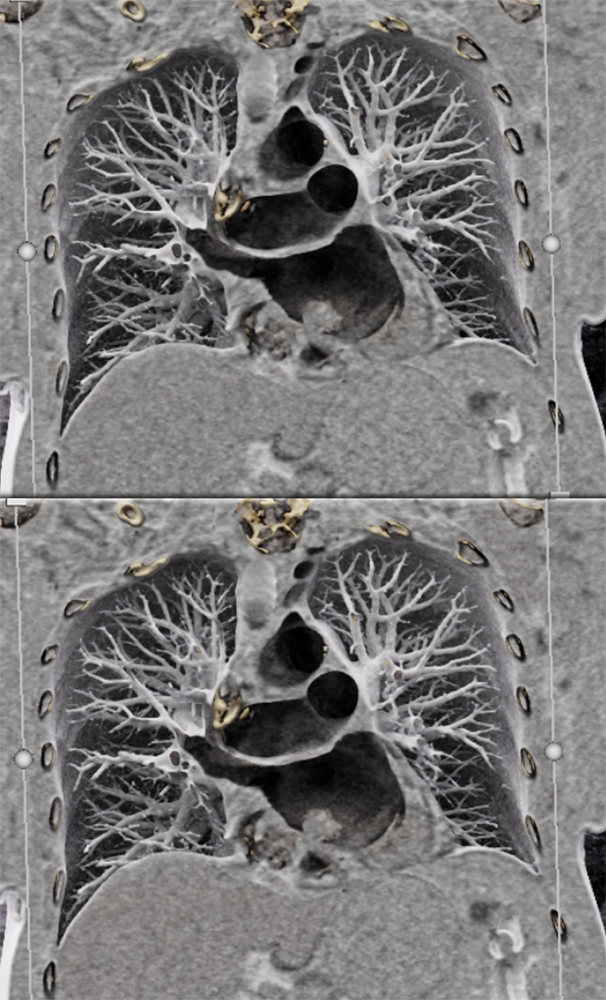

Cardiac Myxoma: CT Findings

“On cardiac CT, approximately two-thirds of myxomas are ovoid with a smooth or lobular shape, with the remainder villous in appearance. When visualized on non-contrast CT, they typically appear hypodense, consistent with blood, and may demonstrate calcifications more often in the right atrial location. On contrast-enhanced cardiac CT, myxomas appear as intracavitary filling defects with heterogeneous con- trast enhancement, though the intensity may be variable depending on their chronicity and whether necrosis or hemorrhage is present.” Cardiac Masses on Cardiac CT: A Review David Kassop et al. Curr Cardiovasc Imaging Rep (2014) 7:9281 |

”Although they can be located in any chamber, most myxomas are located within the left atrium and originate at the interatrial septum. These lesions may have an irregular border, a pedunculated morphology, and be mobile. The size of the tumor is related to the degree of mobility and the potential that the lesion can obstruct the atrioventricular valve.” Cardiac Neoplasms Radiologic-Pathologic Correlation John P. Lichtenberger III et al. Radiol Clin N Am 59 (2021) 231–242 |

” Although computed tomography (CT) is not the preferred method to characterize the tumor, typical findings on a contrast-enhanced CT include a spherical or ovoid mass that is lower in attenuation than surrounding myocardium.” Cardiac Neoplasms Radiologic-Pathologic Correlation John P. Lichtenberger III et al. Radiol Clin N Am 59 (2021) 231–242 |